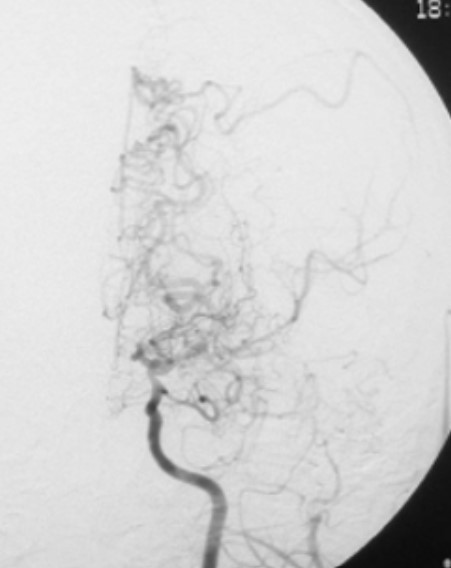

もやもや病とは、脳内の太い血管が何年もかけて少しずつ細くなり、そのあいだに脳梗塞、脳内出血やけいれんなどをおこす病気です。15%は親から子へ遺伝しますが残りはいまだ原因がわかっていません。細くなっていくあいだに脳のもともと細い動脈が必要に迫られて太くなり、血管撮影ではもやもやとけむっているように見えます。この病気は日本人を含めたアジア人に多く、最初にこの病気を英語で報告した日本の先生が、もやもや病と名付け(1969年)、その後この名前が世界中に広まりました。「もやもや」ではなく「もじゃもじゃ」や「もくもく」のように見える場合もありますが、やはり一番しっくりするのは「もやもや」というオノマトペだと思いますので、今から考えてもいいネーミングでした。よくある動脈硬化による脳梗塞と比べてめったになく、十万人に0.3−0.5人のかたが一年で新しくこの病気になると言われています。

もやもや病の脳血管撮影の写真はこのように動脈の先が細くなり、もやもやとした血管の集まりが見られるのが特徴です。